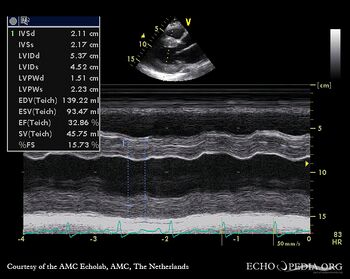

| HCM, diastolic dysfunction

| Courtesy of: AMC Echolab, AMC, The Netherlands

| PLAX: concentric left ventricle hypertrophy, poor function

| M-Mode through left ventricle